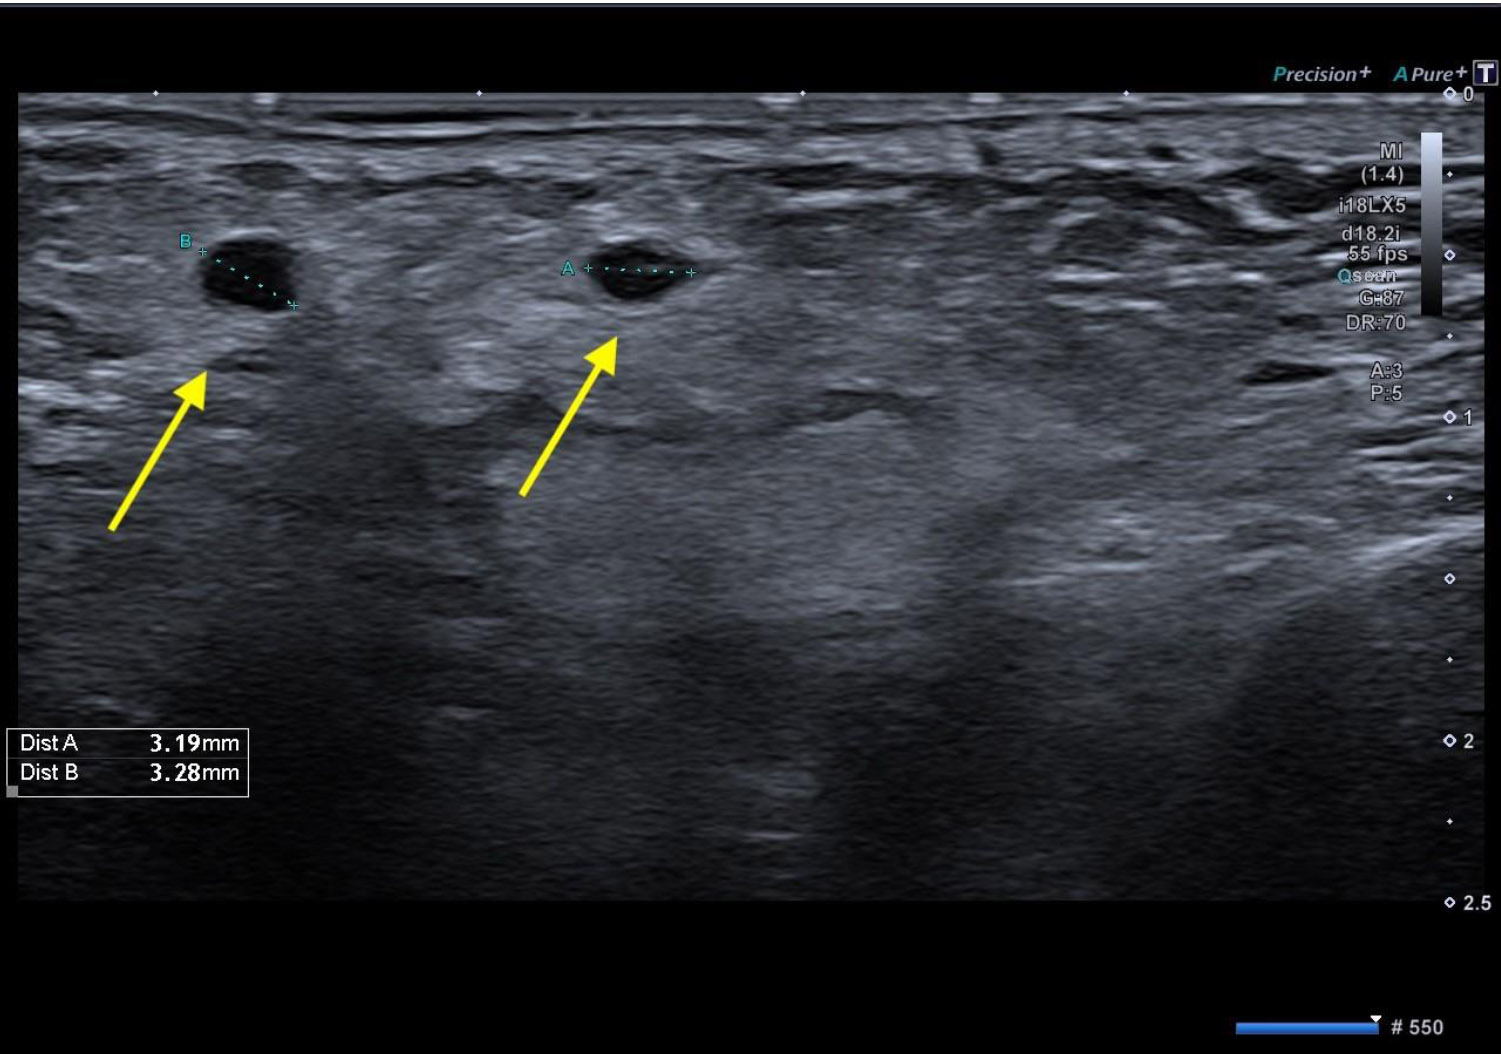

During a 4-day check, the patient reported an almost complete resolution of symptoms, with no signs of inflammation or bleeding visible. A follow-up ultrasound was scheduled, and it revealed two anechoic areas (3 mm in diameter) and a blurred hyperechoic region in the subcutaneous and muscular areas, with no clear boundaries (Fig. 6). Microbiological analysis resulted in negative findings, and facial asymmetry was no longer visible.

Post-operative ultrasonography. Two small anechoic areas of approximately 3 mm in diameter were identified (yellow arrows), along with a poorly defined hyperechoic region within the subcutaneous and muscular tissues, lacking clear demarcation.